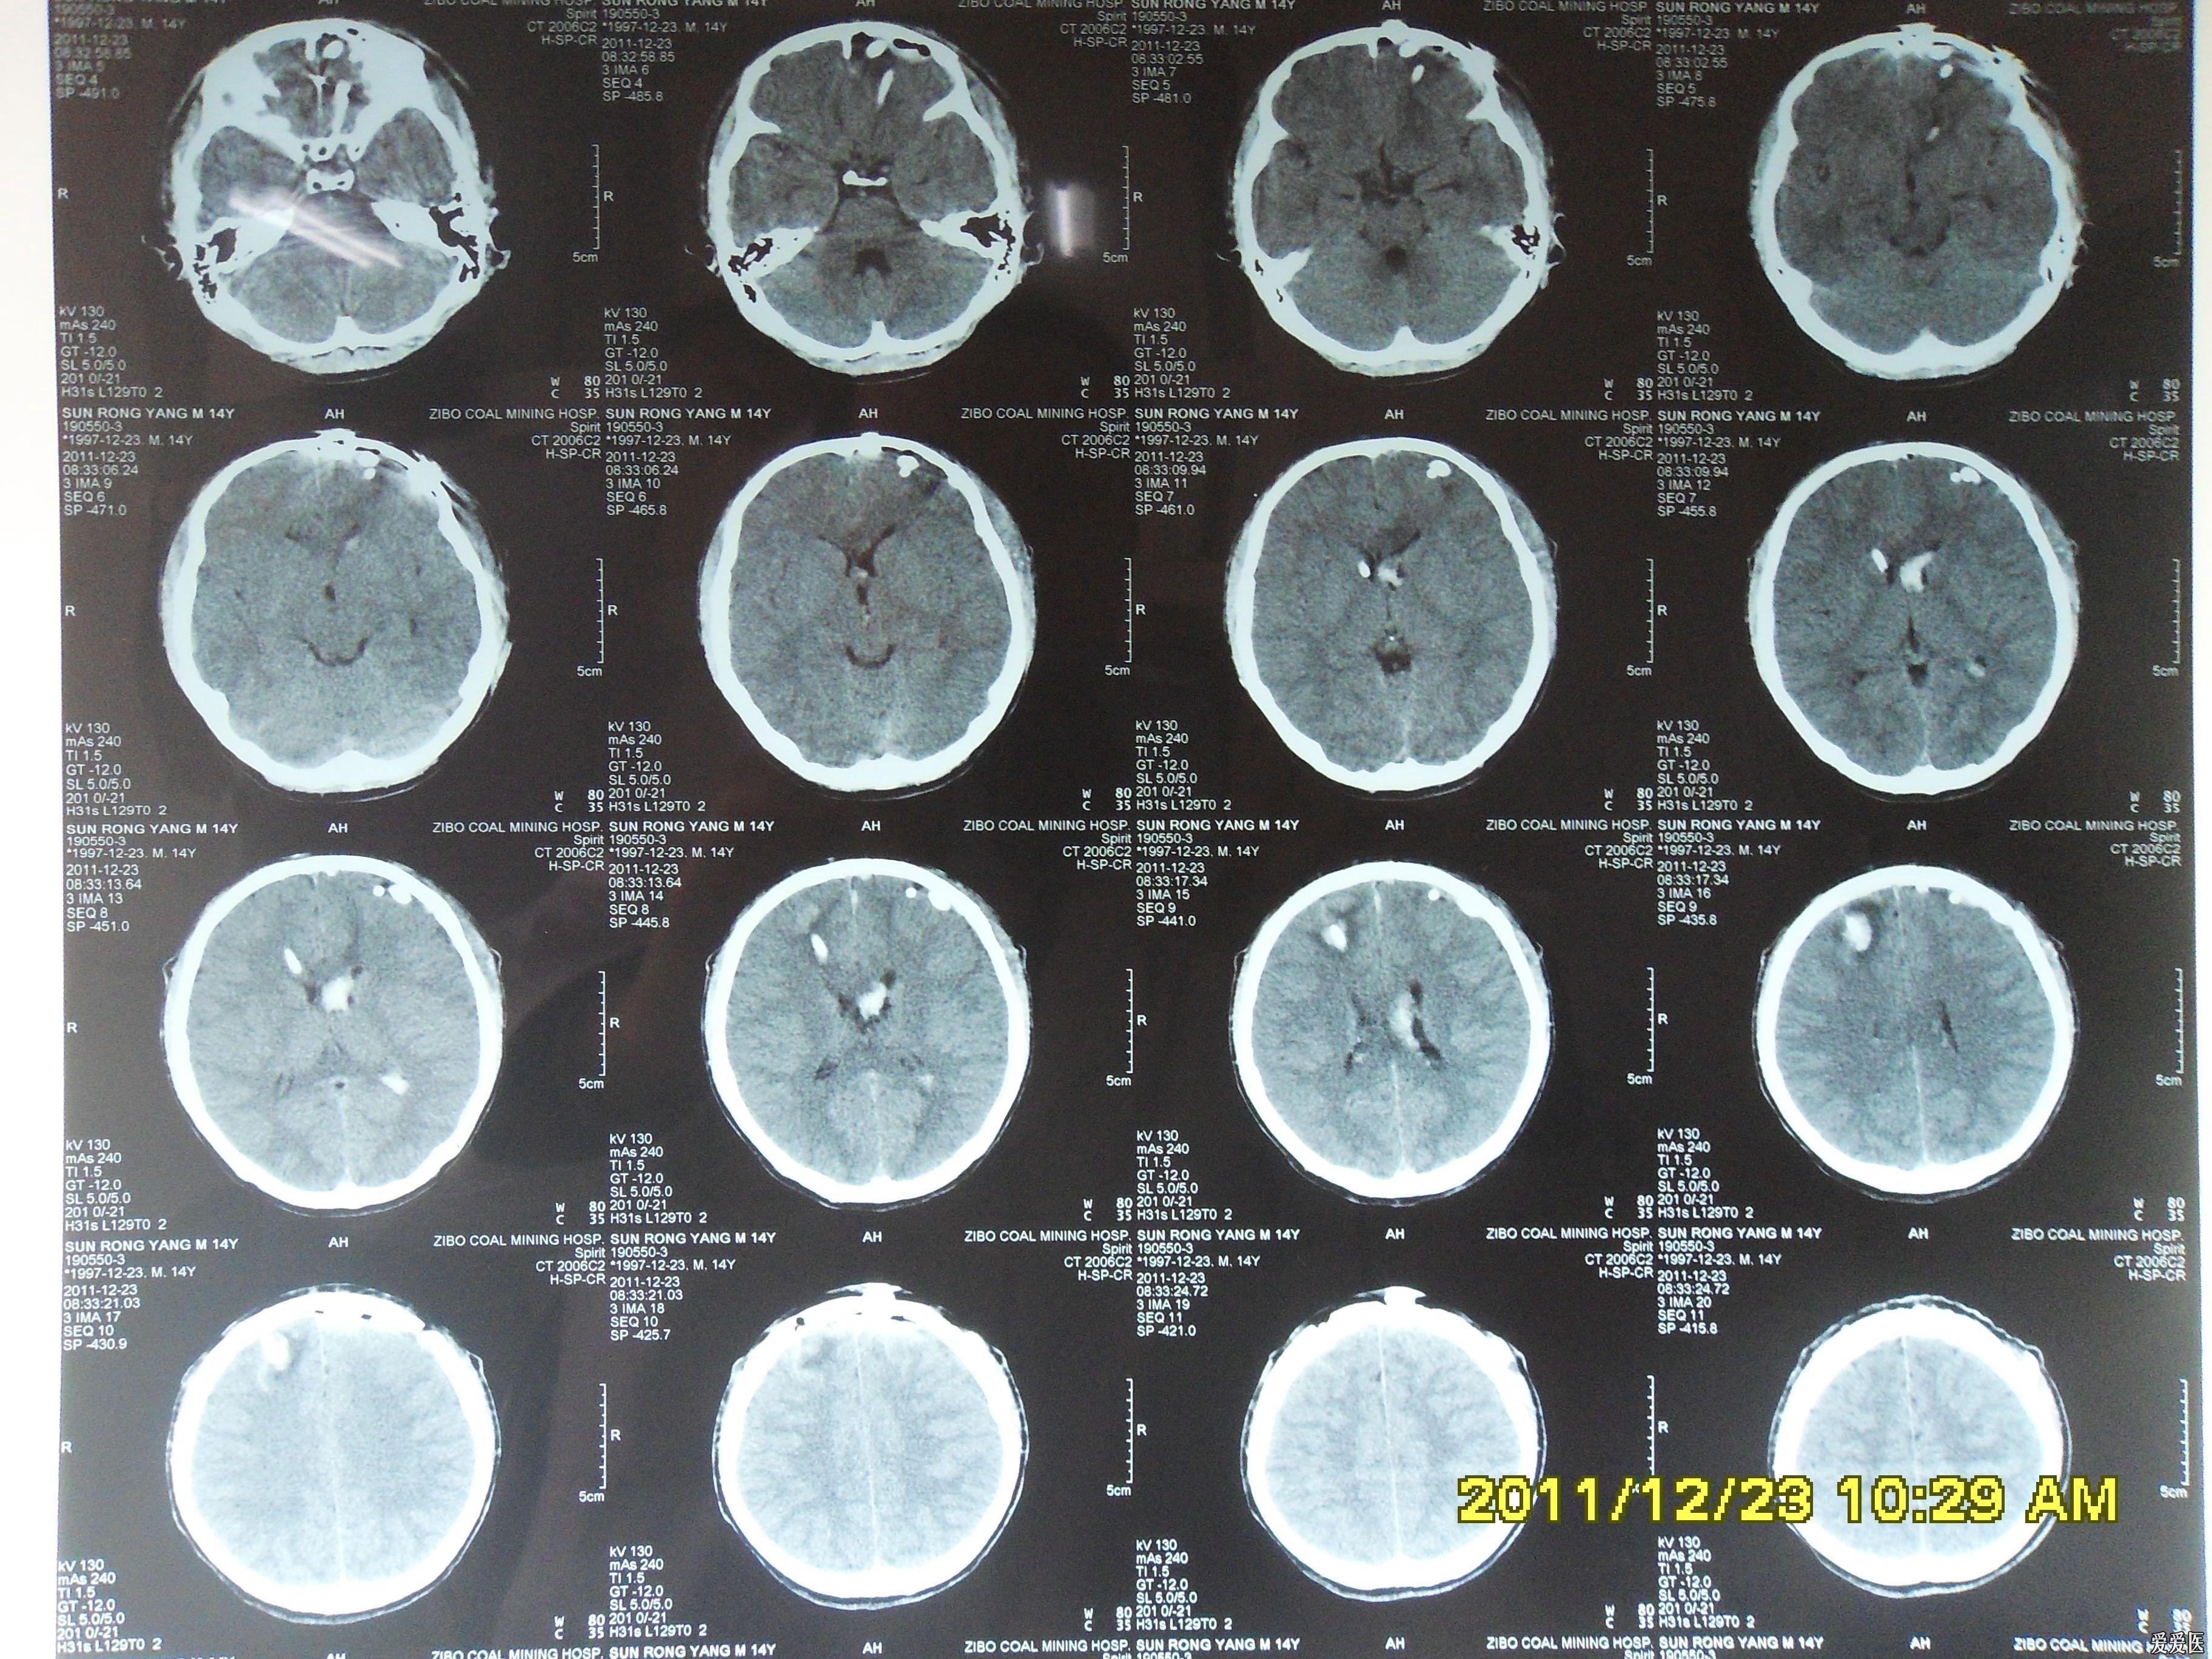

今天做到的病例脑裂畸形

图片尺寸2592x1944

今天做到的病例脑裂畸形

图片尺寸2592x1944

今天做到的病例脑裂畸形

图片尺寸2592x1944

今天做到的病例脑裂畸形

图片尺寸2592x1944

今天做到的病例脑裂畸形

图片尺寸2592x1944